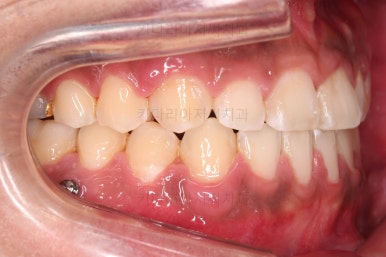

부산교정 장치를 부착했습니다.

이번에 선택하신 장치는 자가결찰 세라믹 장치에요. 스스로 철사를 묶는(결찰) 뚜껑이 달린(자가) 세라믹 성분의 장치인데요.

기능적으로도 우수하고, 세라믹이다 보니 미적으로도 장점이 있습니다.

이번 환자분은 엠파워 클리어라고 하는 장치를 사용했으며 흔히 아신느 클리피씨와 동일한 계열의 장치입니다.

장치 부착 직후의 느낌 참고해 주시고요.